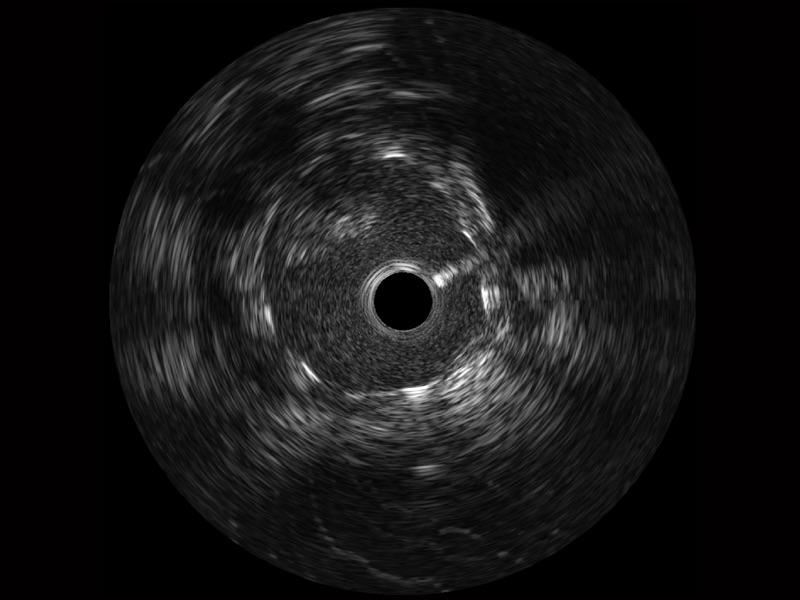

诸侯快讯官网宽频IVUS图像

传统IVUS图像

对比传统IVUS导管成像,诸侯快讯官网宽频IVUS图像的近场支架梁显影更细腻,远场中膜外血管仍清晰可辨,兼顾远中近,兼顾分辨力与穿透深度